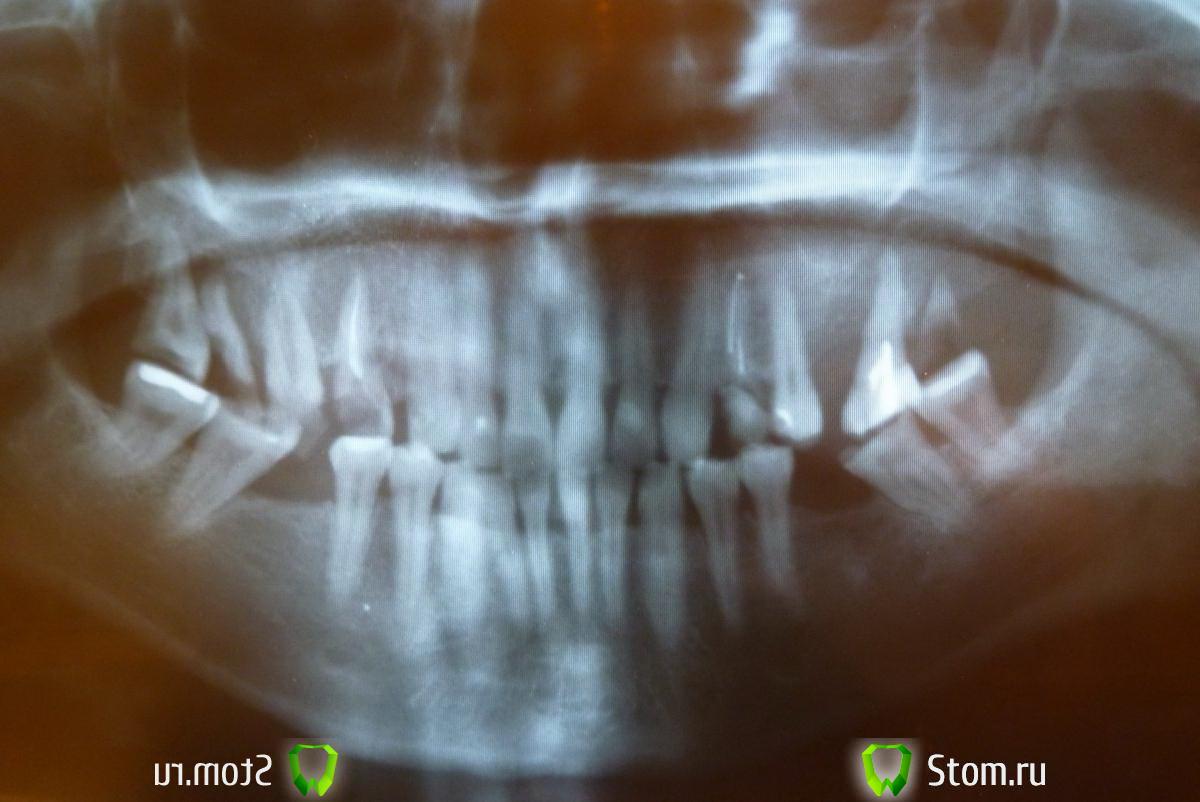

Фрида-77 Опубликовано 18 февраля, 2012 Поделиться Опубликовано 18 февраля, 2012 Хочу заняться зубками, т.к. выпали пломбы.Зубы не болят и не беспокоят. Подскажите,что с ними делать? Реставрация или протезирование? Имплантация отпадает (есть противопоказания).Спасибо,жду ответов. Трудно неспециалисту разобраться ))) Ссылка на комментарий

Фрида-77 Опубликовано 18 февраля, 2012 Автор Поделиться Опубликовано 18 февраля, 2012 Смотрела,вглядывалась...кажется всё наоборот-снимок в зеркальном отражении))) Ссылка на комментарий

DmitrySH Опубликовано 18 февраля, 2012 Поделиться Опубликовано 18 февраля, 2012 У Вас сильная патологическая стираемость зубов. Тут без осмотра в кресле трудно советовать. Ссылка на комментарий

DmitrySH Опубликовано 24 февраля, 2012 Поделиться Опубликовано 24 февраля, 2012 Нет, фото не вариант. Потребуется комплексное лечение: терапия, хирургия, ортопедия, может еще и ортодонтия Ссылка на комментарий